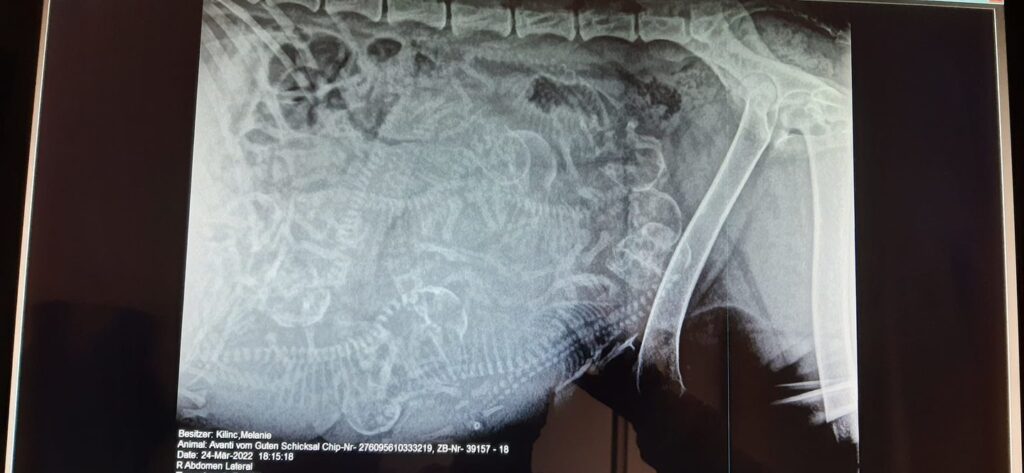

Am Donnerstag gab es einen kleinen Check up und Röntgen (ohne Narkose) für Avanti Mittlerweile hat die dicke 8 kg zugenommen, Bauchumfang beträgt nun 85 cm und ihr geht es prächtig Ich freue mich riesig auf die baldige Geburt der kleinen B-chens ♥️ 9 kleine Hovis konnten wir zählen.

18.03.2022

50. Trächtigkeitstag